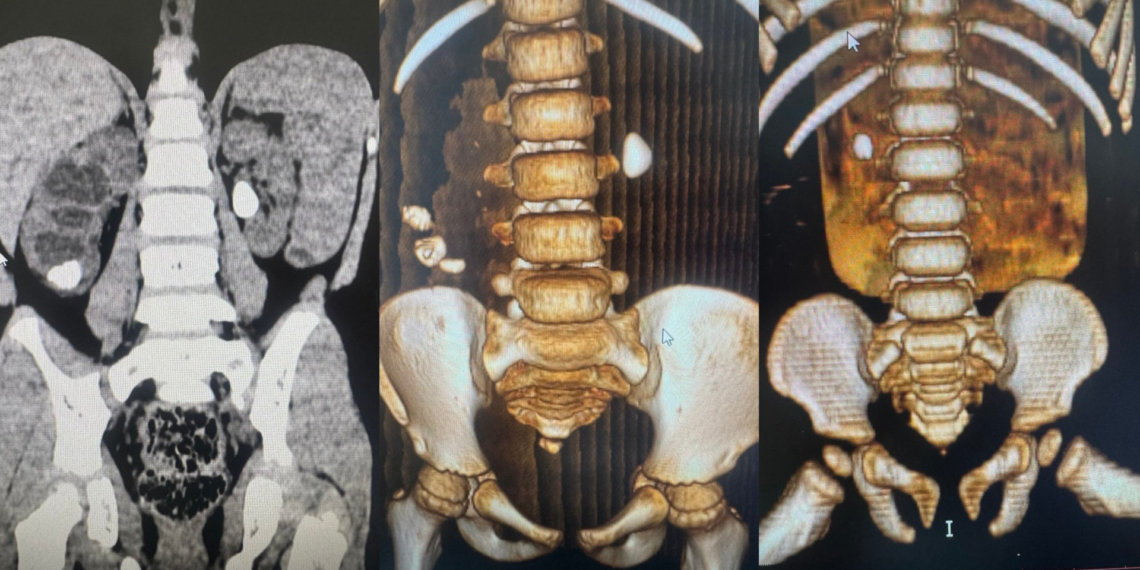

В среднем размер камней у детей составляет 5-7 миллиметров. Рекордным стал показатель — 6 сантиметров. Самым юным пациентом с диагнозом мочекаменная болезнь в 2025 году был малыш в возрасте 11 месяцев.